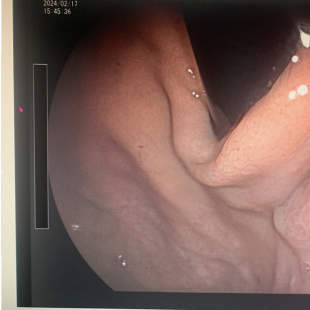

胃镜检查示:胃底前壁靠近贲门处可见一大小约1.1cmx0.9cm的灰白色息肉样黏膜隆起,表面光滑。

胃镜示:胃黏膜可见一大小约1.1cmx0.9cm的灰白色扁平的息肉样黏膜隆起,表面光滑,无溃疡形成。